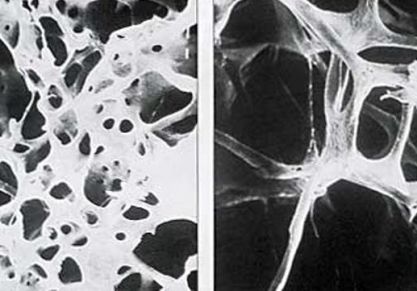

Лечение остеопороза народными средствами: рецепты приготовления

Народная медицина в борьбе с остеопорозом костной ткани. Рецепты лекарств, способы их применения и описание противопоказаний.